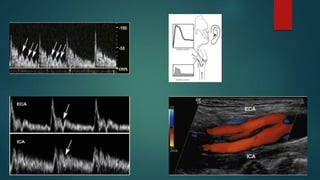

• Escala de grises.

• Doppler color y poder.

• Espectral.

• Transductor de alta frecuencia.

 Flujo cefálico a lo largo del ciclo cardíaco

 Patrón de flujo de baja resistencia.

 Visualización del origen.

 Tamaño: Variable y asimétrico +/- 4mm

 PSV: 30-60 cm/s (< 10 cm/s potencialmente anómalo)

 Vena vertebral.

 Puede verse adyacente y superior a la arteria con flujo caudal.

 Patrón no pulsátil.